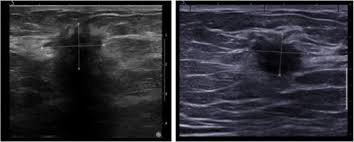

Ultrasound may be particularly useful in detecting abnormalities in patients with dense breasts. Finding breast lumps and seeing change in the size and shape. Ultrasound does not use or. Women or men who develop any of the inflammatory breast cancer early signs should seek medical care immediately to ensure timely treatment. The sound waves pass through the breast and bounce back or echo from various tissues to form a picture of the internal structures of the breast.

As the machine is moved over an area of the breast, the device sends sound waves into the tissue, and it shows an image based on how quickly those waves bounce back to it. Ultrasound does not use or. The lump may shows a combination of clustered tiny cysts and thickened parenchyma (arrows in c) Ultrasound may be particularly useful in detecting abnormalities in patients with dense breasts. Presenting radiologic appearance of breast dcis microcalcifications at breast cancer screening we can see from the chart above that overall, the most commonly occuring mammographic indication of dcis are the crushed stone microcalcifications.

What does breast cancer look like? X trustworthy source mayo clinic educational website from one of the world's leading hospitals go to source research suggests that men are more likely to ignore breast lumps than women, but early. What does breast cancer look like on a mammogram? That said, ultrasound is an extremely fast and powerful tool. Ultrasound does not use or. Ultrasound images are black and white, showing a small portion of the breast at a time. Mammography is the least sensitive imaging. The sound waves pass through the breast and bounce back or echo from various tissues to form a picture of the internal structures of the breast. This may include normal tissue and glands, as well as areas of benign breast changes (e.g., fibroadenomas) and disease (breast cancer). Density is a term used to describe breast tissue that has many glands close together. Ibc is a rapidly progressive, aggressive form of breast cancer associated with a low overall survival rate. Ultrasound is not used on its own as a screening test for breast cancer. If you have calcifications, they'll show up as white spots.